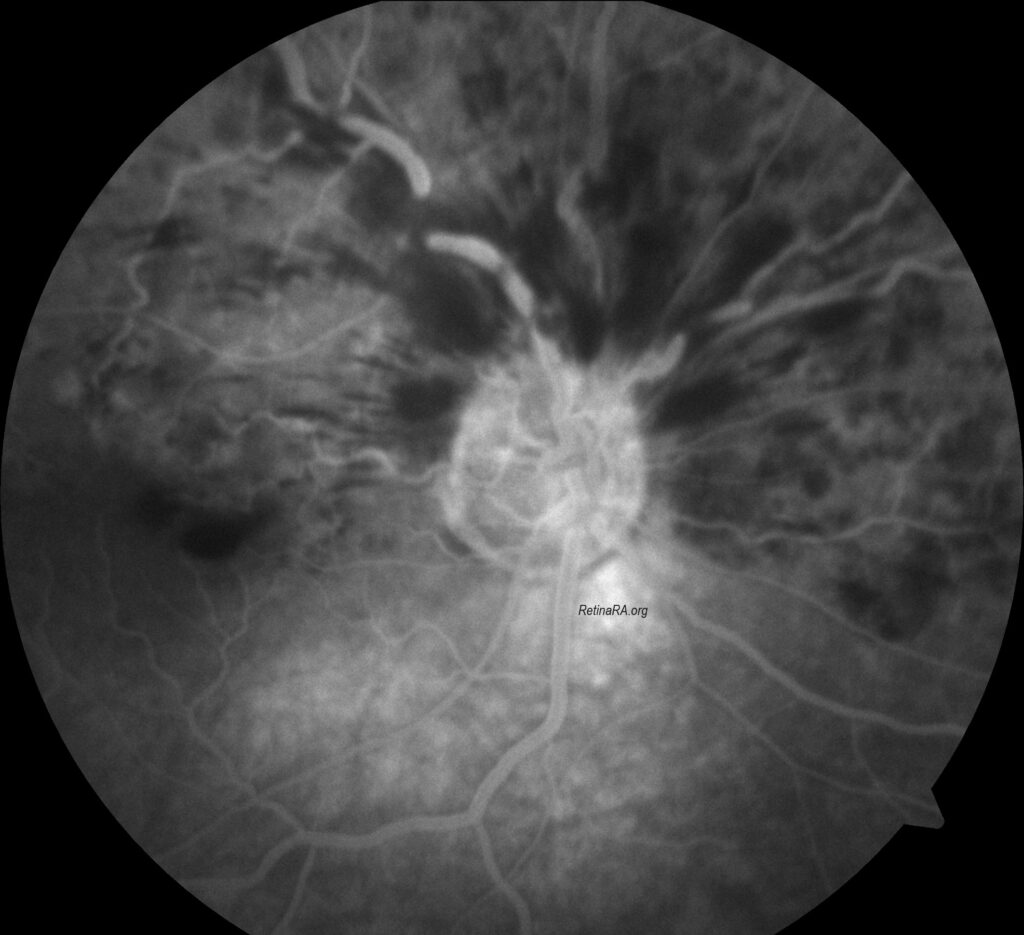

Hemi-CRVO has been shown to be a distinct entity that is clinically and pathogenetically closely related to CRVO and unrelated to BRVO due to fundamental differences between the two. Hemi-CRVO clinically presents as either venous stasis retinopathy or as hemorrhagic retinopathy, usually involving one half of the retina, although occasionally it may involve one third to two thirds of the retina. The clinical features of venous stasis retinopathy and hemorrhagic retinopathy caused by hemi-CRVO are identical to those caused by CRVO. Visual prognosis seems to be better in hemi-CRVO than in total CRVO.

Credit: Kemal Tekin, M.D., from Ulucanlar Eye Training and Research Hospital